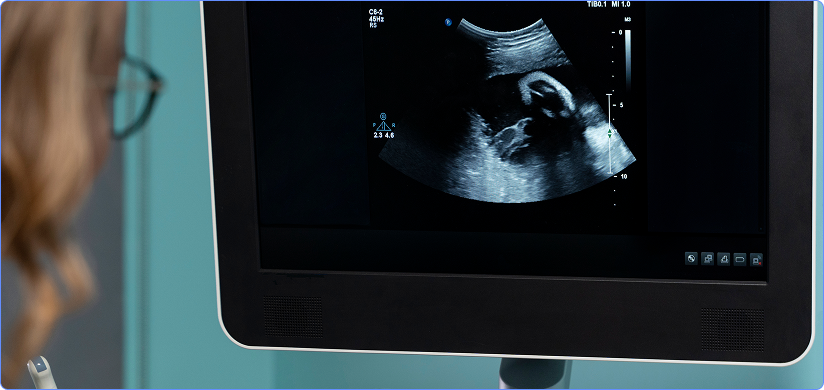

Ultrasound Reporting

Ultrasound (USG) report is a diagnostic document prepared by a radiologist or sonographer after interpreting ultrasound images to identify abnormalities, diseases, or conditions such as cysts, stones, masses, or fluid collections. Ultrasound report is a medical summary of what was seen during an ultrasound (sonography) examination. It explains the appearance, size, and condition of internal organs or structures and helps doctors diagnose problems and plan treatment.

Ultrasound (USG) is an imaging technique uses high‑frequency sound waves (above 20 kHz, typically 3–20 MHz in medicine) to generate real‑time images of the organs, tissues, blood vessels, and a foetus inside the body, used to diagnose conditions, monitor pregnancy, guide procedures, and assess blood flow without using ionizing radiation. These sound waves are transferred into the body by a handheld probe (transducer) to reflect the echoes from tissues, these echoes are converted into the images on a screen by a computer.

Ultrasound reporting we provide remotely refers to the service wherein a diagnostic document is written by our radiologists after analysing the images we received from healthcare institutions. Ultrasound is a unique, noninvasive procedure that allows radiologists to observe anatomical structures and their real-time movements. Generally, although these healthcare institutions might have round-the-clock on-site facilities, there is a lack of specialists to analyze the results. This causes delay in treatment, which is not ideal for urgent or emergency/STAT patients. Remote ultrasound reporting allows rapid analysis ultrasound scans, which reduces turnaround times (TAT).